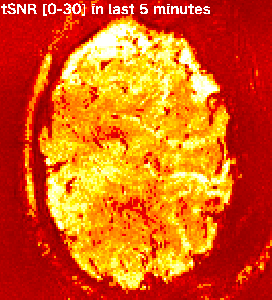

gif_2_annotated renzohuber February 2, 2018February 17, 2018 Published by renzohuber View all posts by renzohuber Published February 2, 2018February 17, 2018